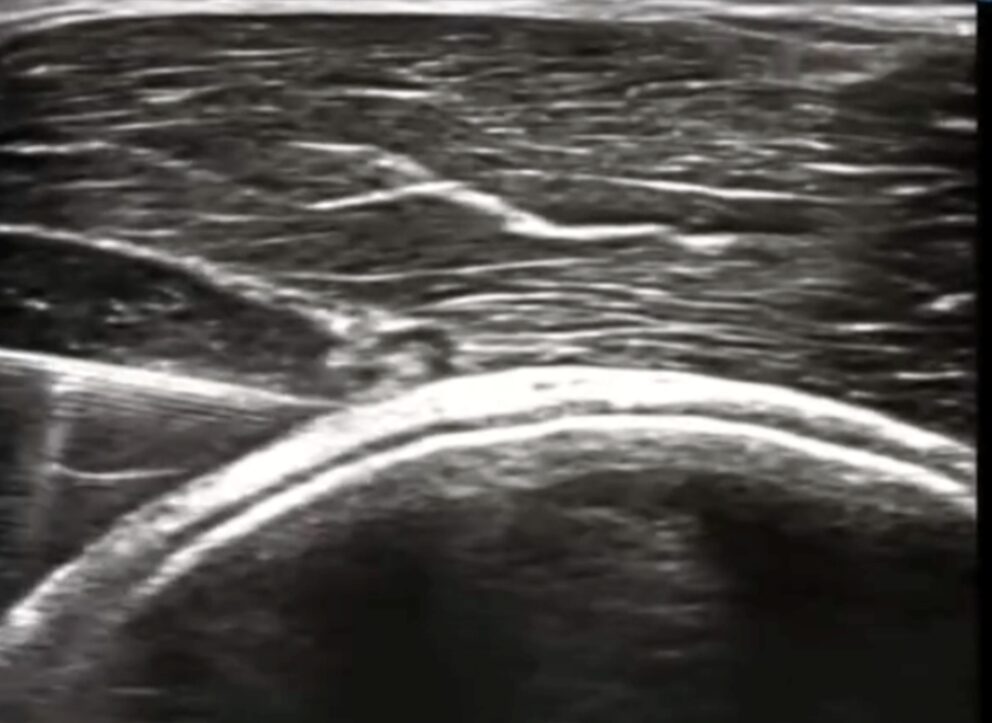

超音波(エコー)による“痛みの可視化”

ここが最も重要なステップです。超音波(エコー)検査装置を使い、痛みの原因となっている部位をリアルタイムの画像で観察します。エコーを用いることで、レントゲンやMRIでは捉えきれない筋膜の重なり、肥厚、神経の腫れや癒着を、患者様ご自身の目で確認することができます(1)。

診断によって癒着部位が特定されたら、いよいよ治療です。ハイドロリリースは、超音波(エコー)で身体の中をリアルタイムに見ながら行うことで、その安全性と効果を最大限に発揮します。

ハイドロリリースは、「ハイドロ(液体)」の力で、癒着した組織を「リリース(剥離・解放)」する治療法です。具体的には、エコーで神経や筋膜、血管の位置を正確に確認しながら、非常に細い注射針を進め、癒着している部位に生理食塩水や低濃度の麻酔薬を注入します。

注入された液体の水圧によって、これまで癒着していた組織の間にスペースが生まれ、物理的に剥がれていきます。これにより、神経や筋膜の滑走性が回復し、圧迫から解放されるのです。

エコーガイド下で行うことの最大の利点は、安全性です。神経や血管をリアルタイムで視認できるため、それらを誤って傷つけるリスクを最小限に抑えることができます。治療は外来で5〜10分程度で完了し、身体への負担も非常に少ないのが特徴です。